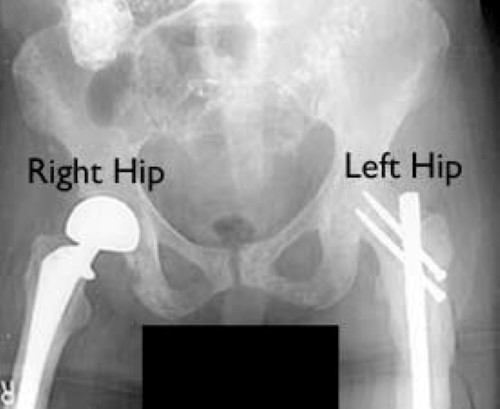

two types of hip stabilization for metastatic bone disease

A woman with advanced metastatic breast cancer to bone with pain in both her right and left hips required different types of surgery to address her problems. A special partial hip replacement was needed on the right because the hip joint was involved. On the left, a special nail was used to strengthen the femur bone below the hip.

Reproduced with permission from Weber K, Lewis V, Randall RL, Lee AK, Spingfield D: An approach to the management of the patient with metastatic bone disease, in Helfet DL, Greene WB (eds): Instructional Course Lectures, Volume 53. Rosemont, IL, American Academy of Orthopaedic Surgeons, 2004.